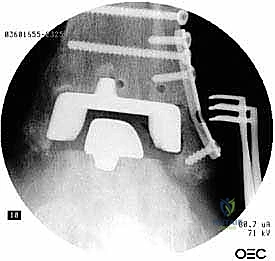

خطوات جراحة مراجعة مفصل الكاحل (Agility) بالتفصيل

تعتبر غرفة العمليات ساحة لإظهار البراعة الجراحية. عملية المراجعة تستغرق عادة من 3 إلى 5 ساعات وتتم عبر الخطوات المعقدة التالية:

يتم تخدير المريض (نصفياً أو كلياً) واستخدام عاصبة (Tourniquet) لتقليل النزيف. يتم تعقيم الطرف السفلي وتجهيز أجهزة الأشعة المرئية (C-arm) داخل الغرفة.

الخطوة الخامسة: تركيب المفصل الجديد أو الدمج

يتم إدخال المفصل الجديد المخصص للمراجعة، والذي يحتوي غالباً على سيقان (Stems) تدخل عميقاً في عظمة الساق وعظمة الكاحل لضمان الثبات الميكانيكي. في حال وجود كسور في الكعب، يتم تثبيتها في هذه المرحلة.